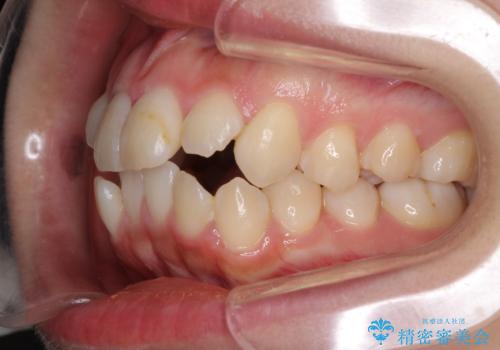

- 口元の突出感を気にして来院された患者様です。

診断の結果、上顎左右第一小臼歯4本抜歯により、叢生を解消するとともに口元を引っ込めていくことが望ましいと判断しました。

抜歯矯正による口元の改善にはワイヤー矯正が望ましいのですが、ダンサーとしての仕事を行っているため、インビザラインにて治療を行うこととしました。